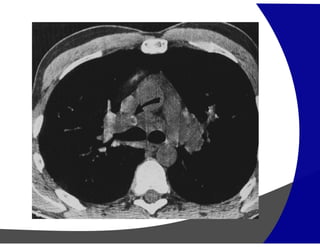

Espessamento dos septos interlobulares

Edema Pulmonar

Linfangite Carcinomatosa

Predomina:

• Espessamento liso dos septos

• Veias pulmonares dilatadas

• Vidro fosco

• Distribuição decúbito dependente

• Espessamento irregular ou nodular

• Espessamento dos feixes broncovasculares

• Distribuição não dependente do decúbito

Espessamento dos septosinterlobulares Predomina: Edema Pulmonar • Espessamento liso dos septos • Veias pulmonares dilatadas • Vidro fosco • Distribuição decúbito dependente Linfangite Carcinomatosa • Espessamento irregular ou nodular • Espessamento dos feixes broncovasculares • Distribuição não dependente do decúbito